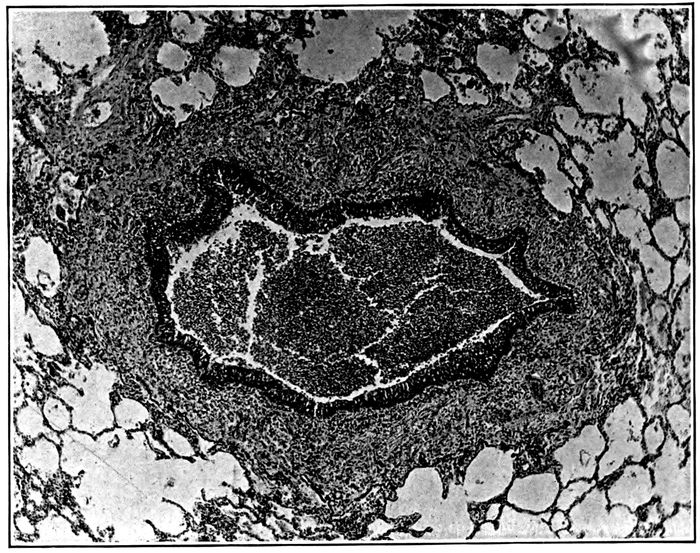

| 2. | Acute bronchopneumonia with nodules of peribronchiolar consolidation and purulent bronchitis | 167 |

| 3. | Acute bronchopneumonia with peribronchiolar consolidation | 169 |

| 4. | Acute bronchopneumonia with peribronchiolar consolidation | 170 |